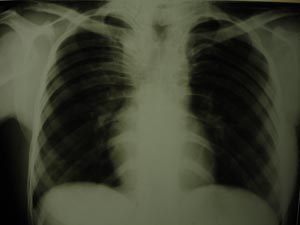

Paratracheal opacity

This is paratracheal opacity, mainly of upper mediastinum. To differentiate lateral view will be helpful.